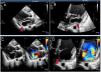

Echocardiographic evaluation (Figure 1) demonstrated posterior mitral leaflet (PML) prolapse with thick-walled aneurysm in the submitral area; cavity size 5.1 × 4.0 cm with to and fro flow into the cavity, with severe mitral regurgitation (MR), no vegetation and thin rim of pericardial effusion. Cardiac contrast-enhanced CT-scan (CECT) (Figure 2) also showed aneurysmal dilatation at the base of the LV along the mitral annulus with prolapse of PML into the left atrium (LA). Both LA and LV were dilated.